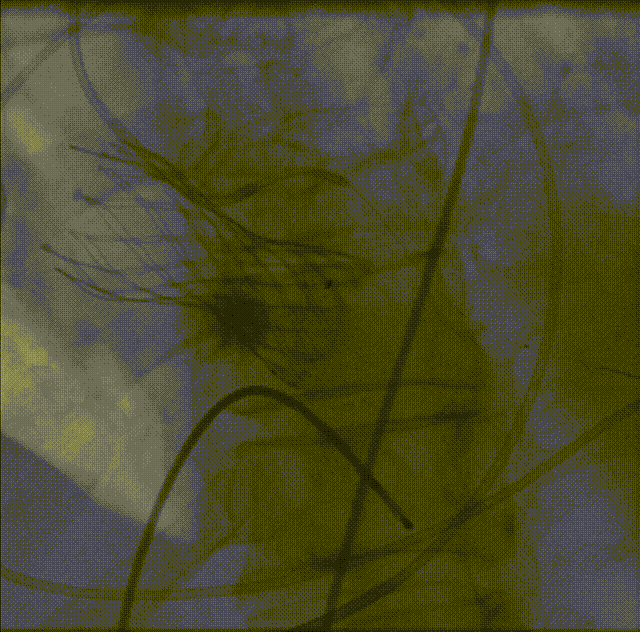

26VenusAplus+snare

瓣膜内22mm球囊后扩张,左冠无显影

LM烟囱支架植入4.0*30mm